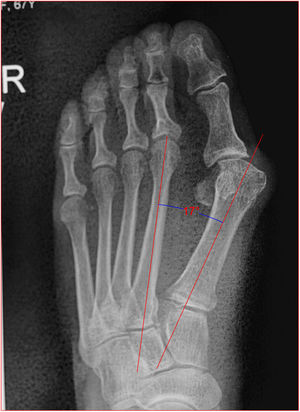

Angulo de valgo: es la intersección del ejes longitudinales del primer metatarsiano y de la falange proximal del hallux. Normal hasta 15 grados (fig. 5).

Angulo intermetatarsianoEs el ángulo entre los ejes longitudinales de primer y segundo metatarsiano, normalmente es menor de 12 grados, cuando esta aumentado se llama metatarso primo varo o aducto y deberá corregirse con osteotomía (fig. 9).